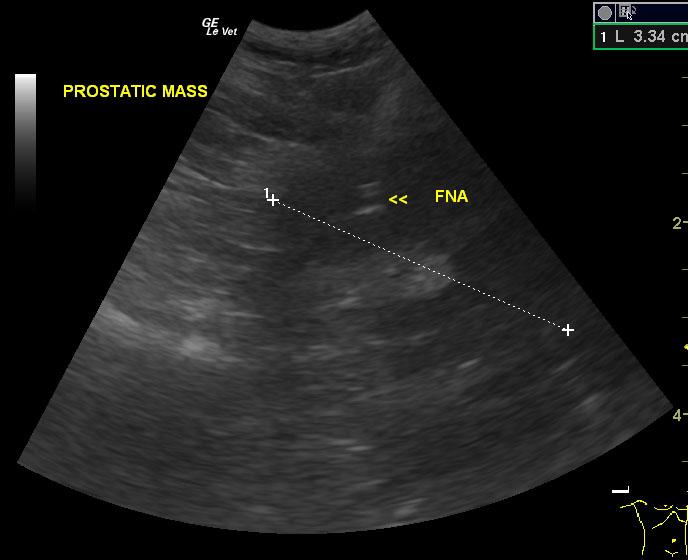

A 15-year-old NM West Highland White terrier dog was presented for evaluation of polydipsia, polyuria and possible bladder stones noted on radiographs. Abnormalities on CBC and serum biochemistry were thrombocytosis, neutrophilia, and hyperalbuminemia. Urinalysis was not performed owing to financial constraints however an abdominal ultrasound prescription was approved.